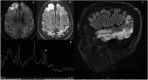

Monogenic diseases, although rare, should be always considered in the diagnostic work up of vascular dementia (VaD), particularly in patients with early onset and a familial history of dementia or cerebrovascular disease. They include, other than CADASIL, Fabry disease, Col4A1-A2 related disorders, which are well recognized causes of VaD, other heritable diseases such as mitochondrial encephalopathy, lactic acidosis, and stroke-like episodes (MELAS) and cathepsin-A related arteriopathy strokes and leukoencephalopathy (CARASAL). MELAS, caused by mtDNA (80% of adult cases m.3243A>G mutations) and more rarely POLG1 mutations, has minimum prevalence of 3.5/100,000. CARASAL, which is caused by mutations in the CTSA gene, has been described in about 19 patients so far. In both these two disorders cognitive features have not been fully explored and are described only in case series or families. This review paper is aimed at providing an update on the clinical manifestations, with particular focus on cognitive aspects, but also neuroradiological and genetic features of these less frequent monogenic diseases associated with VaD.